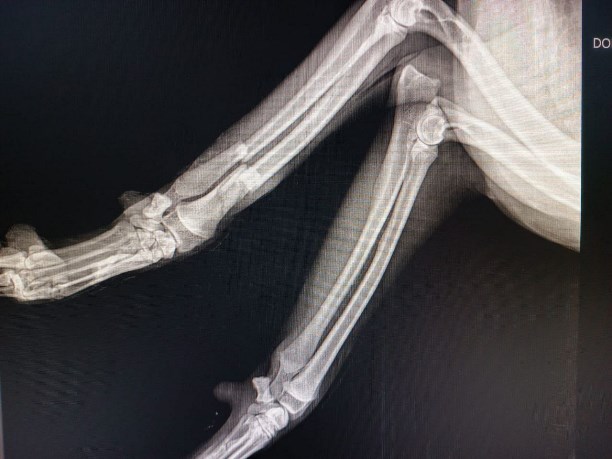

В Фонде помощи бездомным животным "Право на жизнь" сообщили, что у пса диагностировали перелом нижней челюсти, перелом локтевой и лучевой костей, пневмоторакс, контузия легких. После стабилизации состояния предстоит сложная операция.